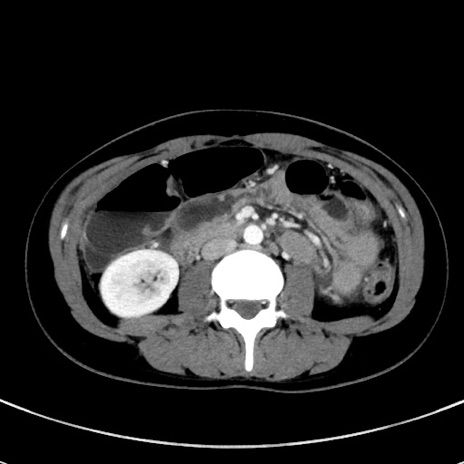

症例17(横断像)

【症例】20歳代女性

【主訴】嘔吐、下腹部痛

【現病歴】昨日夕食後に嘔吐し下腹部痛が出現。本日になっても嘔吐持続し改善しないため来院。

【身体所見】意識清明、BT 37.2℃、BP 108/67mmHg、腹部:平坦、やや硬、下腹部正中から右にかけて圧痛あり、反跳痛軽度あり、tapping pain(+)。

【データ】WBC 13600、CRP 14.94